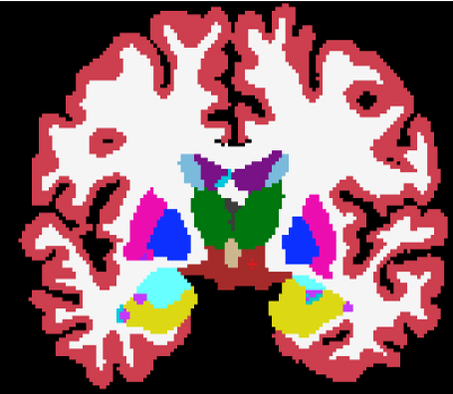

(a) SPGR

(b) ASEG

(c) MALF

(d) PSACNN

(e) Manual

(f) SAMSEG

(g) CNN

In this experiment we compare the accuracy of PSACNN against other methods on the GE14 dataset comprising 14 subjects scanned on a 1.5 T GE Signa scanner with the SPGR (spoiled gradient recalled) sequence (, ms, , voxel size= mm3). All the subjects have expert manual segmentations generated with the same protocol as the training data, but the manual labels are visibly different than training data, with a much thicker cortex (Fig. 9(e)). This is likely because the GE14 SPGR scans (Fig. 9(a)) present a noticeably different GM-WM image contrast than the MPRAGE training data. Consequently, as seen in Fig. 10, all methods show a reduced overlap, but the unaugmented CNN (red boxplot) has the worst performance of all as it is unable to generalize to an SPGR sequence (despite white matter peak intensity standardization). Some obvious CNN errors are for small subcortical structures such as hippocampus (yellow in Fig. 9(g)) labeled as thalamus (green label). PSACNN (ALL Dice=) on the other hand, is robust to the contrast change due to pulse sequence-based augmentation, and produces segmentations that are comparable to the state-of-the-art algorithms such as SAMSEG (ALL Dice=) and MALF (ALL Dice=) in accuracy, with 1–2 orders of magnitude lower processing time.